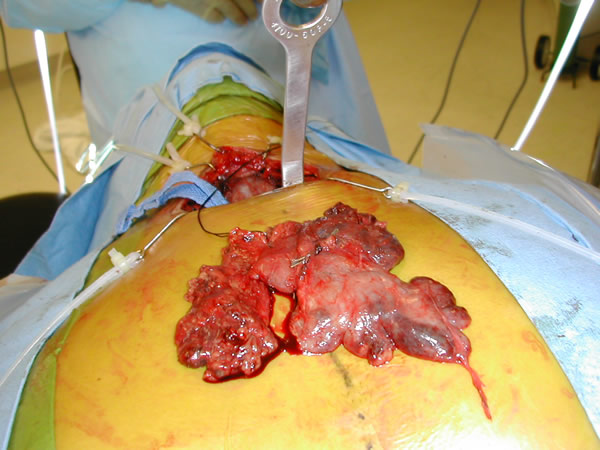

The plane just posterior to the sternum is developed bluntly with a finger and the Rultract retractor is placed and the skyhook used to elevate the sternum (Figure 5A & B, Video 3) [1]. The inflatable pressure bag posterior to the patient is now deflated, allowing the anterior mediastinum to further expand as the middle mediastinum falls away.

| Figure 5a & 5b: Rultract retractor in place. |